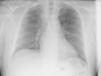

Tomografía axial computarizada de tórax sin contraste (debido a la extravasación de contraste intravenoso) (fig. 2): imagen de masa de partes blandas que ocupa gran parte del mediastino superior derecho, que parece extenderse cranealmente hasta la región supraclavicular derecha, compatible con voluminoso proceso neoformativo localmente muy avanzado, que con muy alta probabilidad engloba estructuras mediastínicas, en particular la VCS, compatible con la información clínica; engrosamiento pleural anterior en el lóbulo pulmonar superior derecho (LSD) y nódulo subcisural en el lóbulo inferior derecho; área de afectación pulmonar anterosuperior en LSD sugerente de neumonitis distal o de incipiente linfangitis carcinomatosa; derrame pericárdico y pleural derecho.

TC de tórax sin contraste. Imagen de masa de partes blandas que ocupa gran parte del mediastino superior derecho, parece extenderse cranealmente hasta la región supraclavicular derecha (voluminoso proceso neoformativo localmente muy avanzado, que engloba estructuras mediastínicas, en particular la vena cava superior, compatible con la información clínica; signos de incipiente linfangitis carcinomatosa; derrame pericárdico y muy discreto pleural derecho).